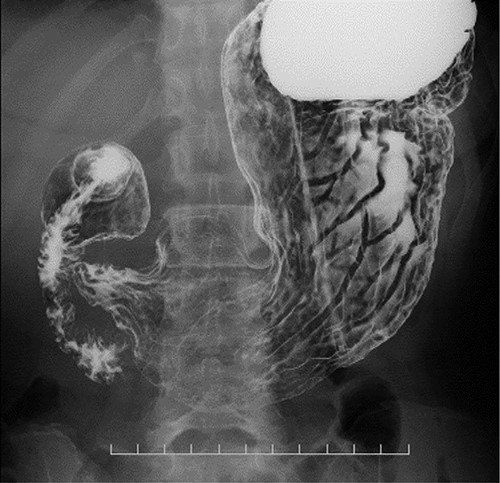

CT images showing a horizontal section of the esophagus; CT image shows circumferential wall thickening with infiltrative changes in the middle part of the thoracic esophagus.

Preoperative computed tomography (CT) and barium meal studies were performed. The CT findings showed circumferential wall thickening with infiltrative change at the middle of the intrathoracic esophagus, with luminal dilation of the oral side of the stenotic esophagus (Figs 2, 3). The barium meal study showed no abnormal findings in the stomach (Fig. 4). Thoracoscopic esophagectomy was performed with the patient in the semi-prone position, followed by esophageal reconstruction using a gastric tube with the patient in the supine position. The operation was started with bilateral lung ventilation using a single-lumen endotracheal tube. A four-port thoracoscopic technique was used as follows: an observation port with a 10-mm scope was placed at the ninth intercostal space at the line of the inferior scapular angle, and two 5-mm ports and one 12-mm port for the intrathoracic procedures were placed at the third, fifth and seventh intercostal spaces, respectively, at the posterior axillary line (Fig. 5). Pneumothorax was created using 10 mmHg of CO2 to deflate the lung to achieve a better operative field. The pleura and connective tissue around the thoracic esophagus showed severe inflammatory and fibrotic changes. In particular, the middle thoracic esophagus was strongly adherent to the arch of the azygos vein and the tracheal bifurcation.